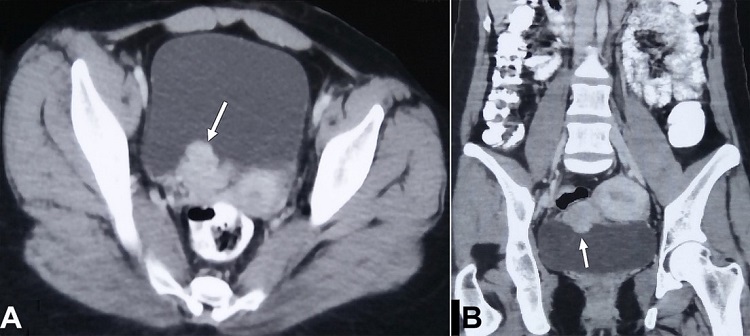

A 21-year-old woman was referred to the Urology Department for management of a high-grade invasive urothelial carcinoma of the urinary bladder, reported on a biopsy performed outside. The only morphological examination was done, and immunohistochemistry (IHC) had not been performed. She had a single episode of gross painless hematuria one month back, for which she had been evaluated. On evaluation, she was asymptomatic, with no remarkable physical examination. Her pulse was 76/min, blood pressure was 110/70mm Hg, and respiratory rate was 18/min. Her blood and urine workup were within normal limits. The abdominal and pelvic contrast-enhanced computed tomography (CT) revealed a nodular and polypoidal enhancing mass from the right posterior wall of the urinary bladder (Figure 1).

An 81-year-old man was referred to the Urology Department to manage a high-grade, poorly differentiated carcinoma of the urinary bladder, reported on a biopsy performed outside. He had a history of repeated episodes of gross hematuria, weight loss, and reduced appetite. On evaluation, he was found to be cachexic, with pallor and icterus. He was anemic, with raised bilirubin and mildly altered liver enzymes. The contrast-enhanced CT scan showed a lobulated enhancing bladder mass with a paravesical extension (Figure 3), abdominal lymphadenopathy and multiple liver metastases